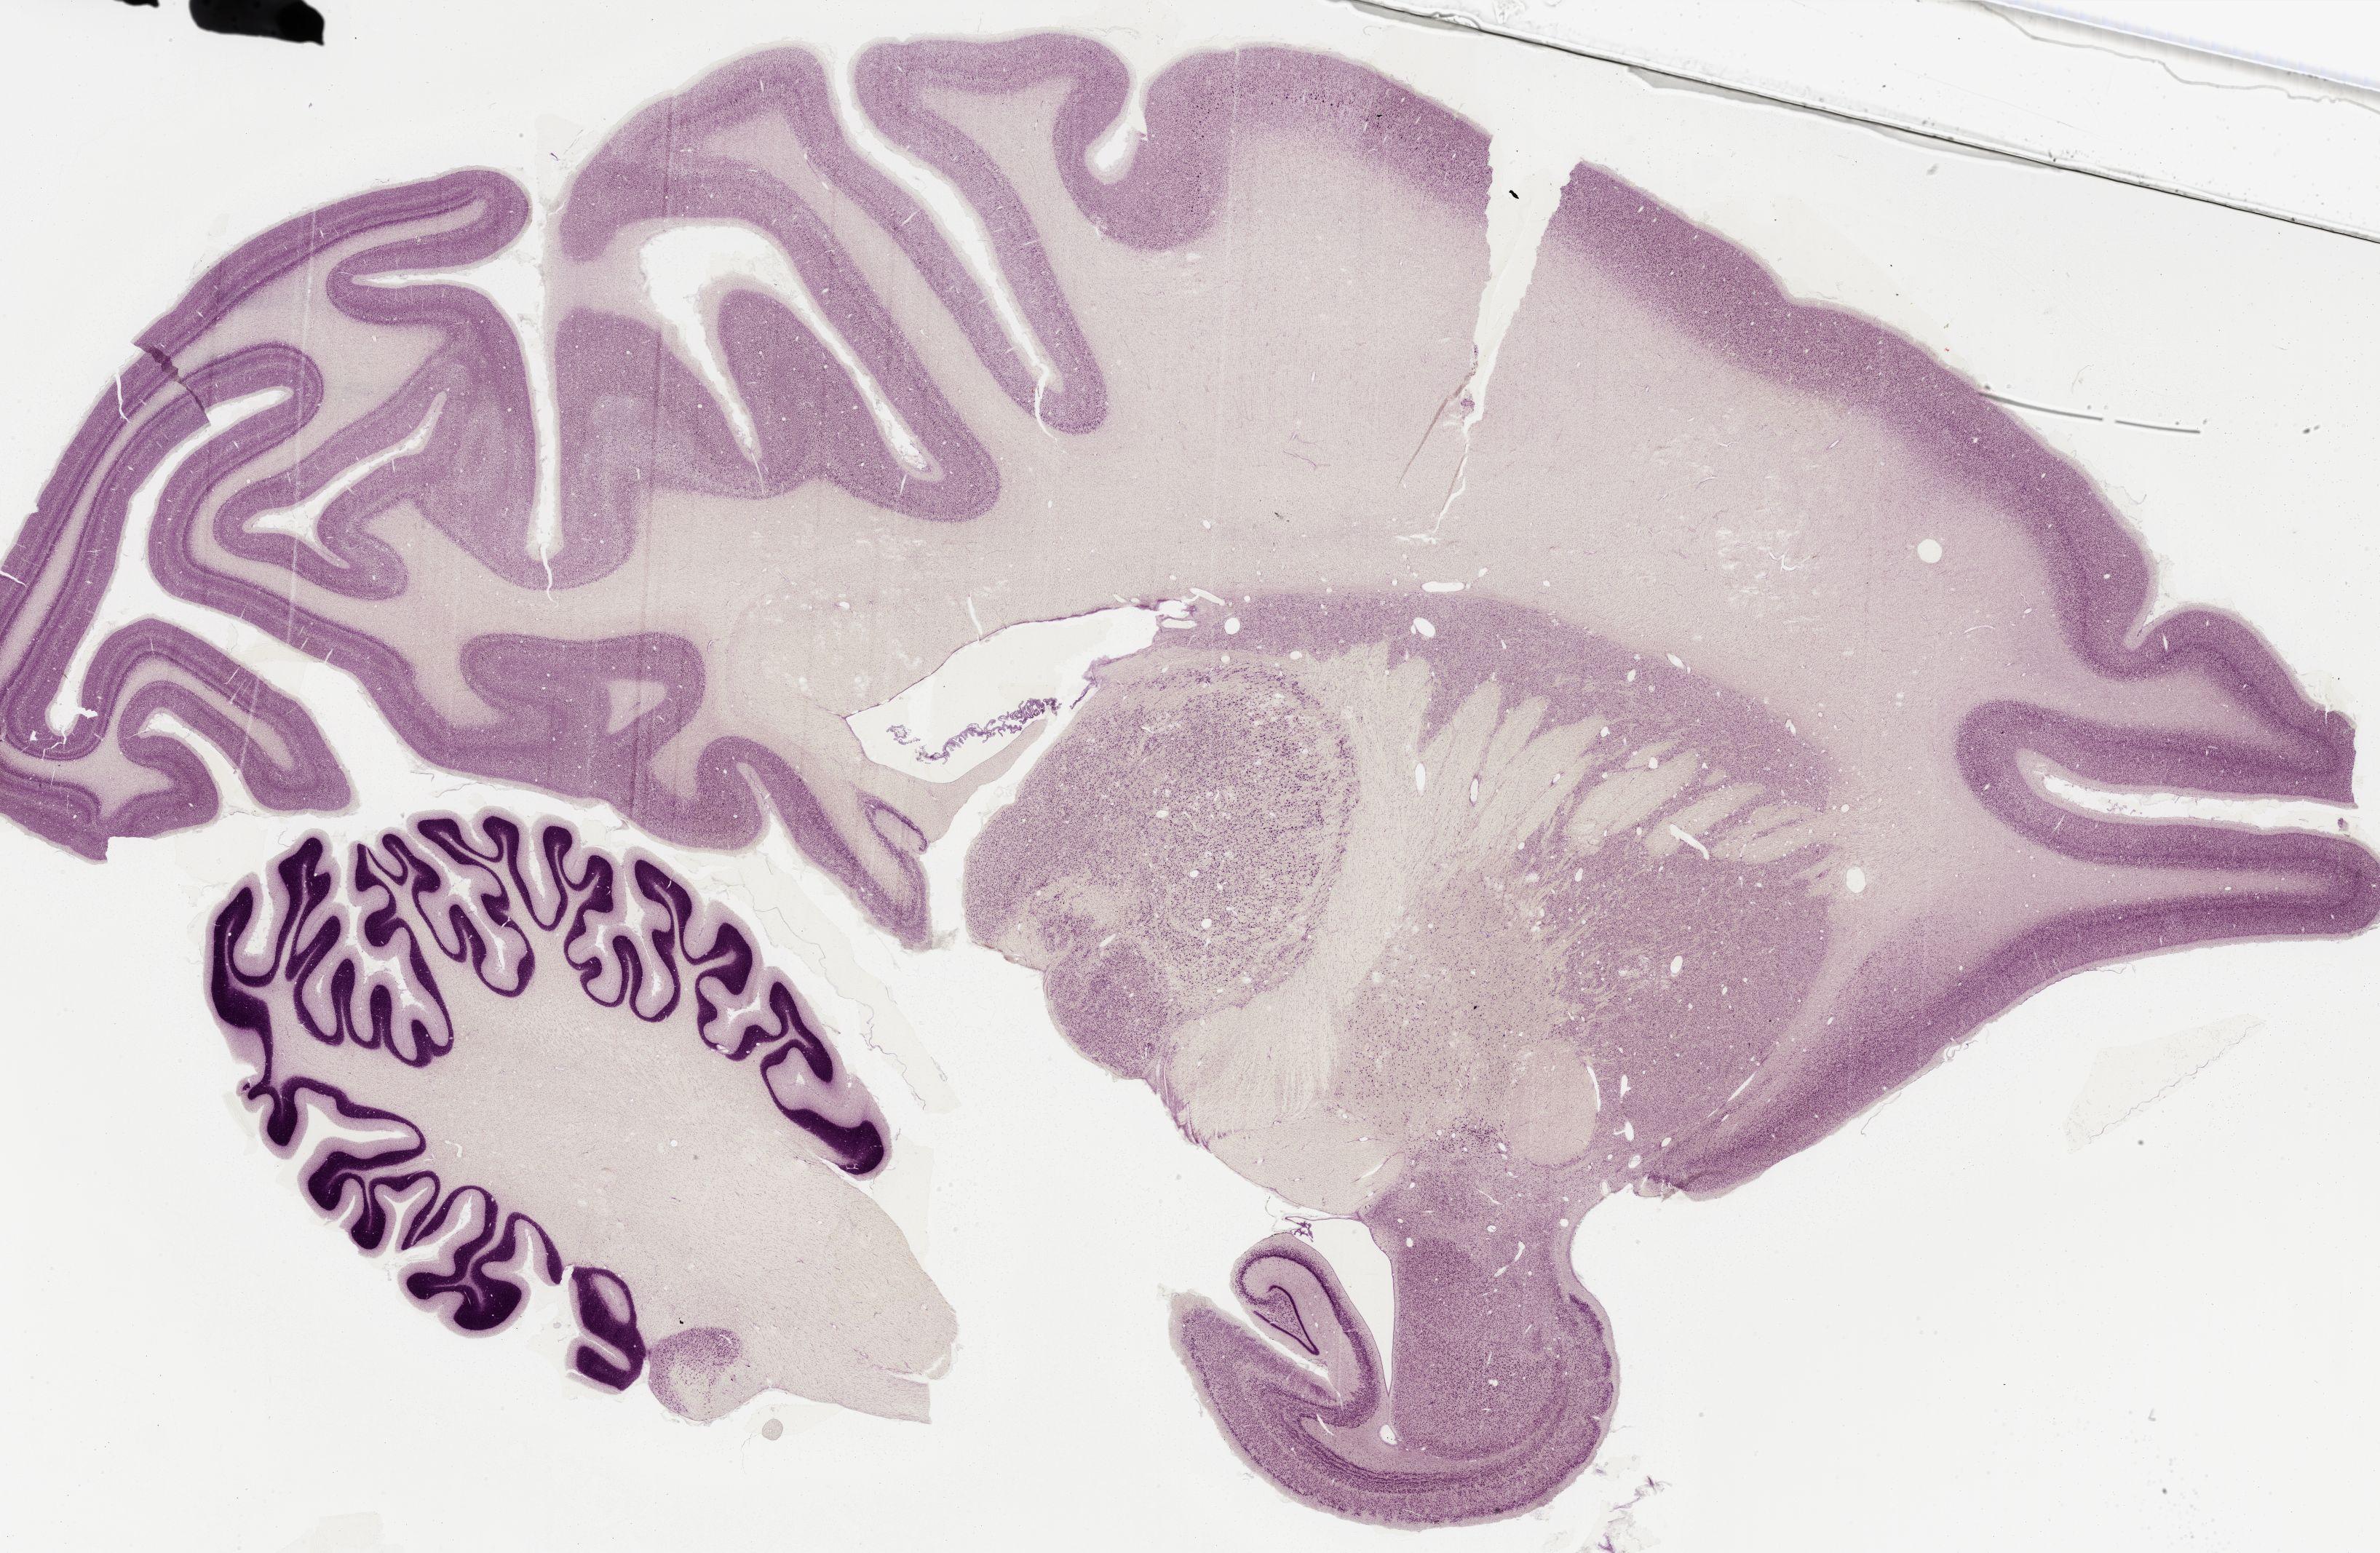

Datasets -> Macaca Mulatta -> Nissl, sagittal, histo, Whole-Brain, adult

[ Metadata ]   ·   Source: Edward G. Jones

Displaying Sections 161 thru 200 of 295 Sections for this Dataset

0367 - labeled